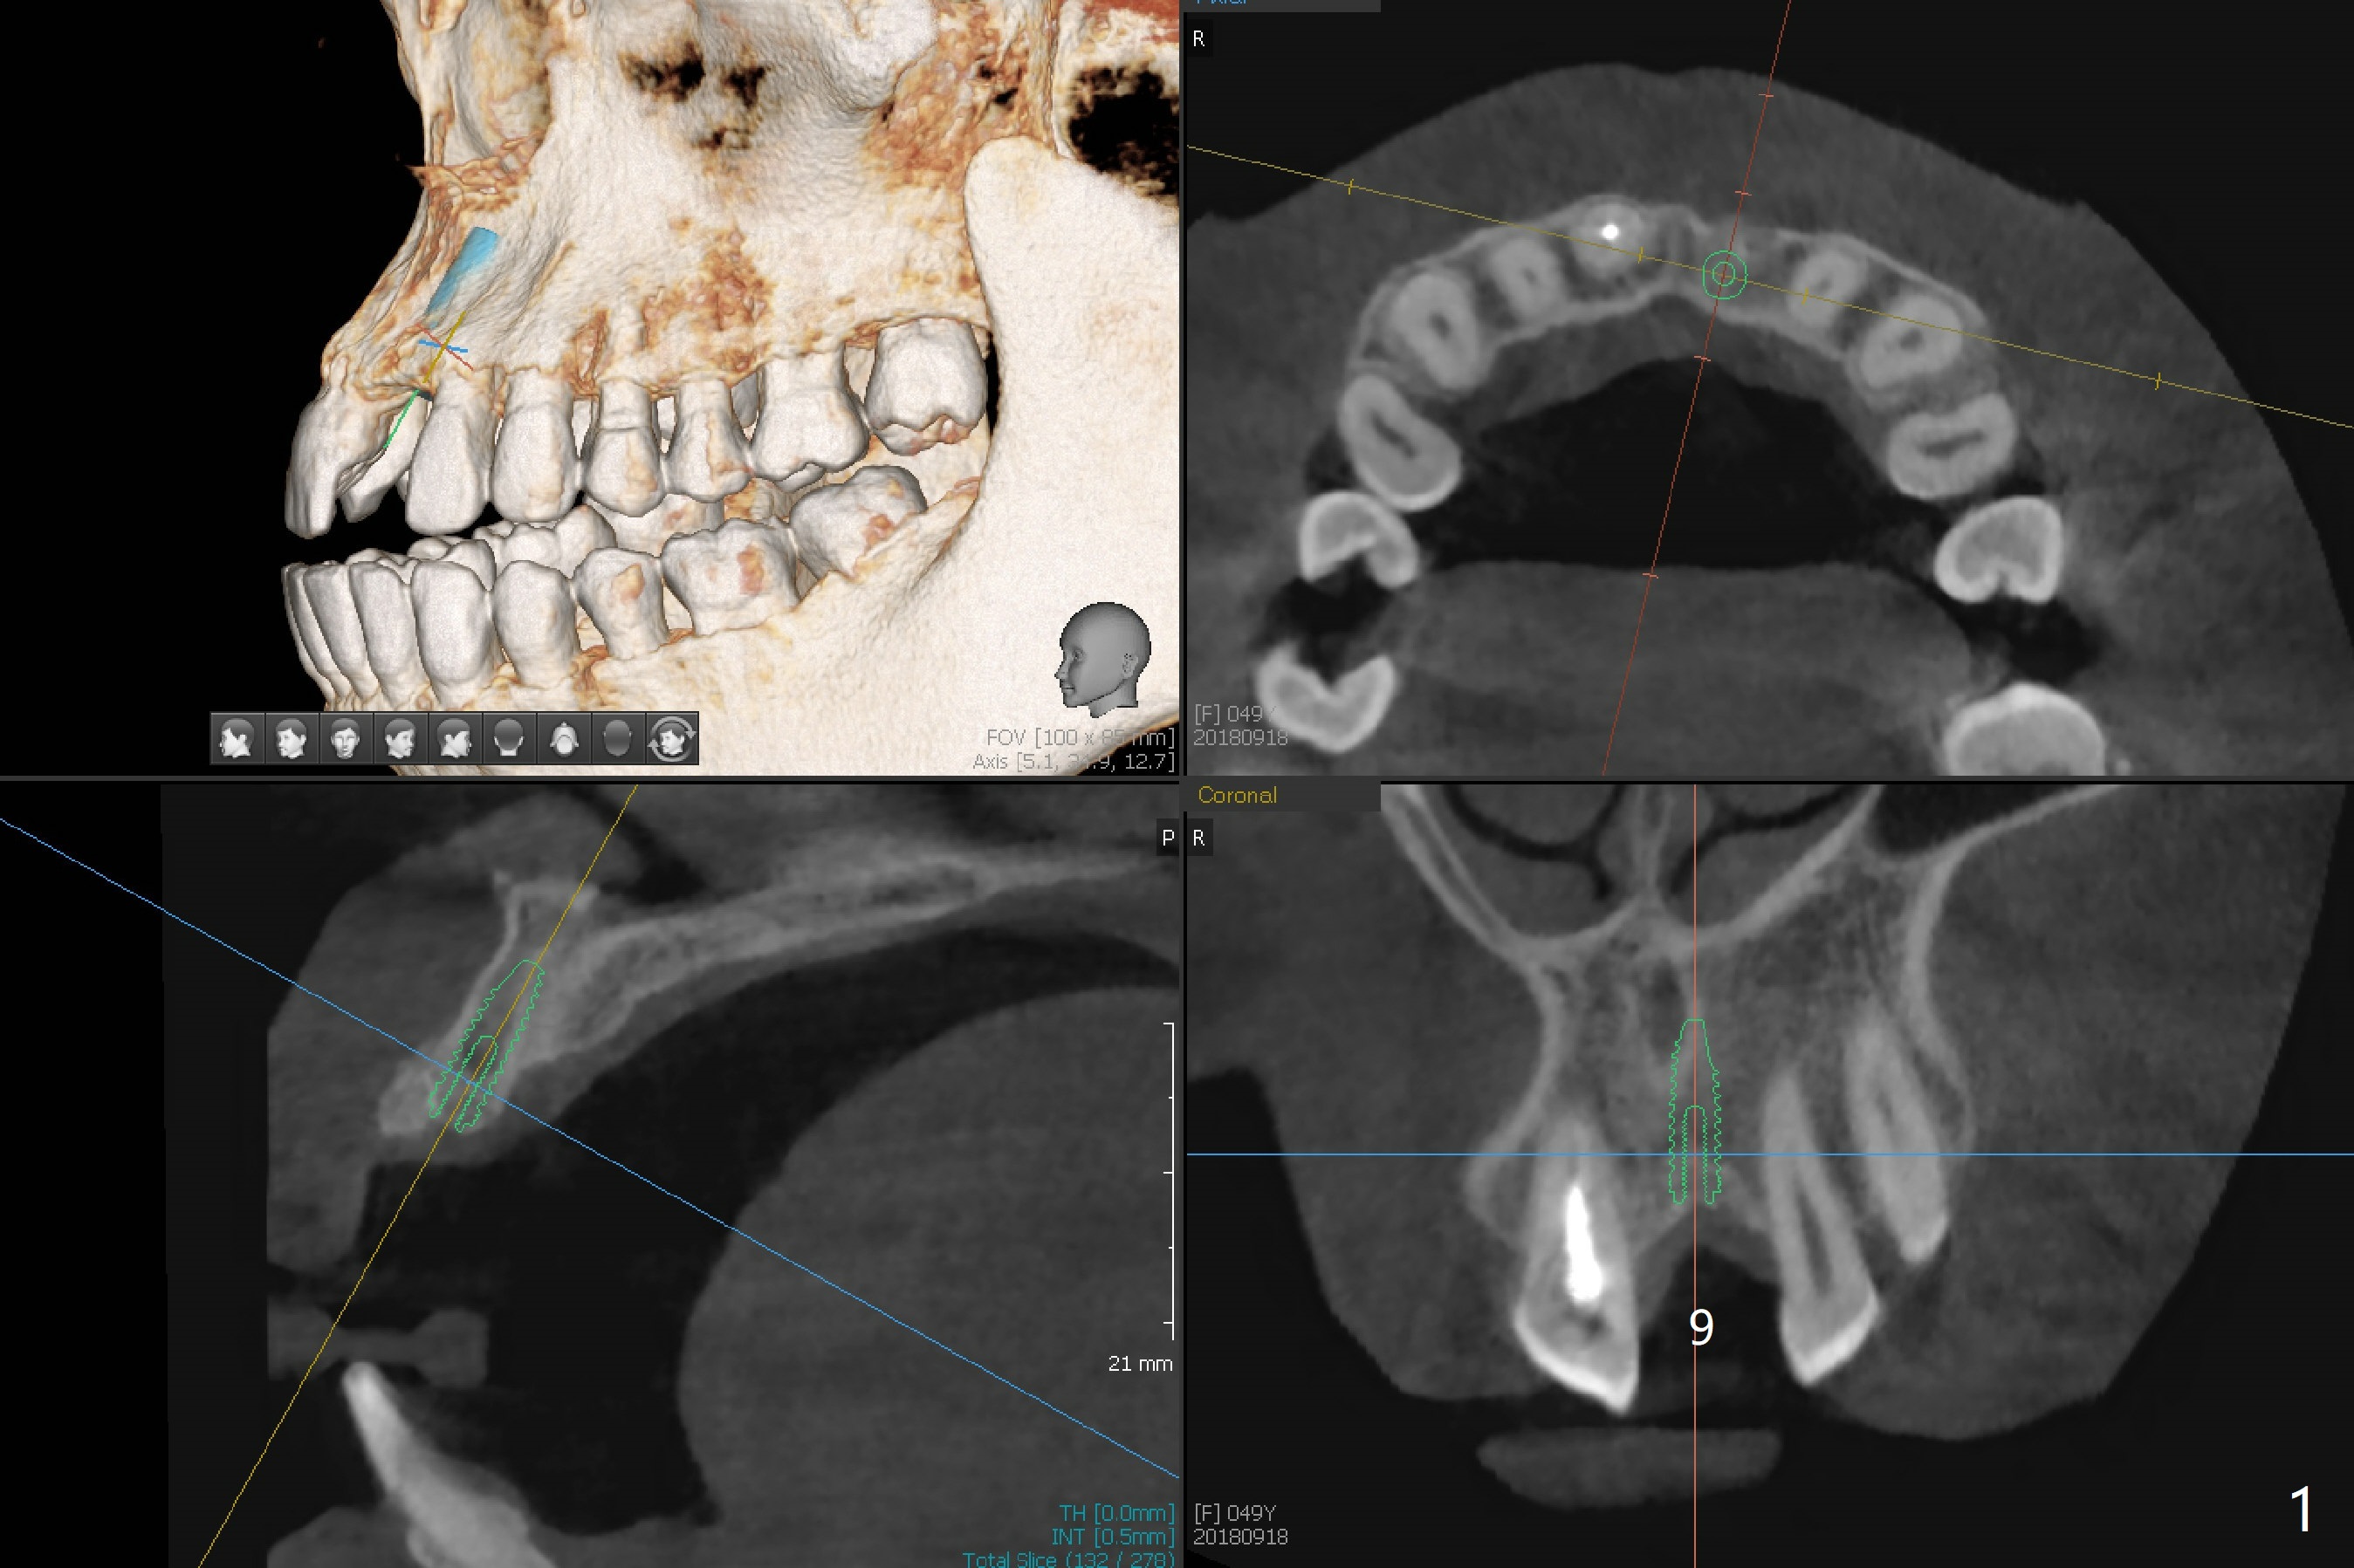

PFM FPD Removal to Reduce CT Metal Scattering

The #8/9 cantilever Maryland bridge of a 49-year-old woman is debonded. After its removal, CBCT is taken for guide (Fig.1). The atrophic ridge apparently accepts a 3.5x11.5 mm implant (Fig.1,3, as compared to Fig.2).